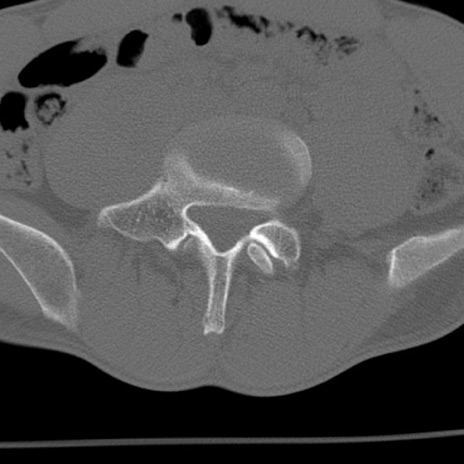

症例3 腰椎CT(横断像)

腰椎CT